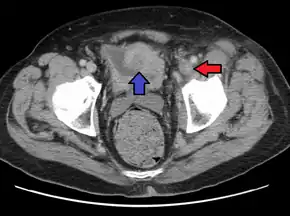

PCD is best diagnosed with contrast venography, but venous duplex ultrasonography is used more commonly. Magnetic resonance and computed tomography venography can also be used.[4]